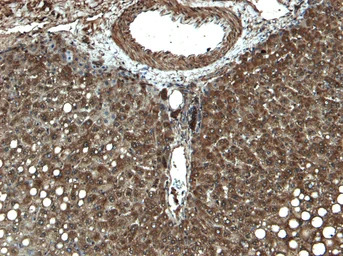

IHC-P analysis of human liver tissue using GTX89375 CYP3A4 antibody, Internal.

Antigen retrieval : Heat induced antigen retrieval with citrate buffer pH 6